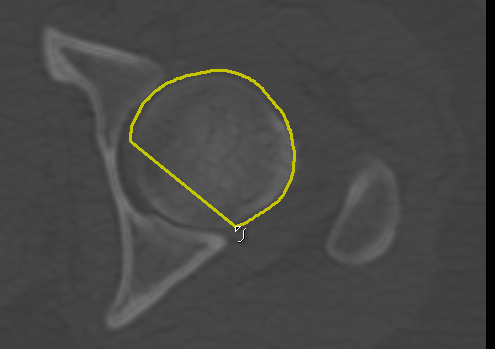

Adds a new path in Snap mode to the current group of paths. You use the Snap tool to create a path by simply dragging inside a feature on a 2D view. The contour line will automatically snap to the gradient that defines the edges of the targeted feature. Do the following to draw a path in Snap mode:

The Snake settings, which include points distance, normal search options, and path rigidity, help control the internal forces that resist deformation when paths are iterated. The Snake settings also include the energy minimization criteria.

Determines the distance (in screen pixels) when drawing paths and is used by the Repulsor tool to push path points. Increasing this parameter will result in downsampling and a smoother path, while decreasing this parameter is recommended for following more angular features. NOTE This parameter may need to be reduced if mesh surfaces are unintentionally closed after generation. |